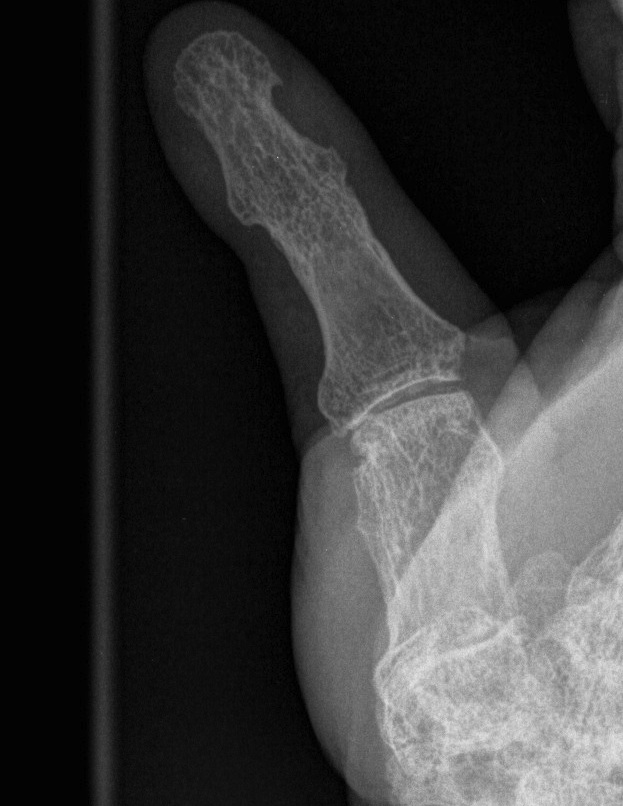

Type VI - Arthritis Mutilans

- destruction and instability MCPJ / IPJ

- arthrodesis only option